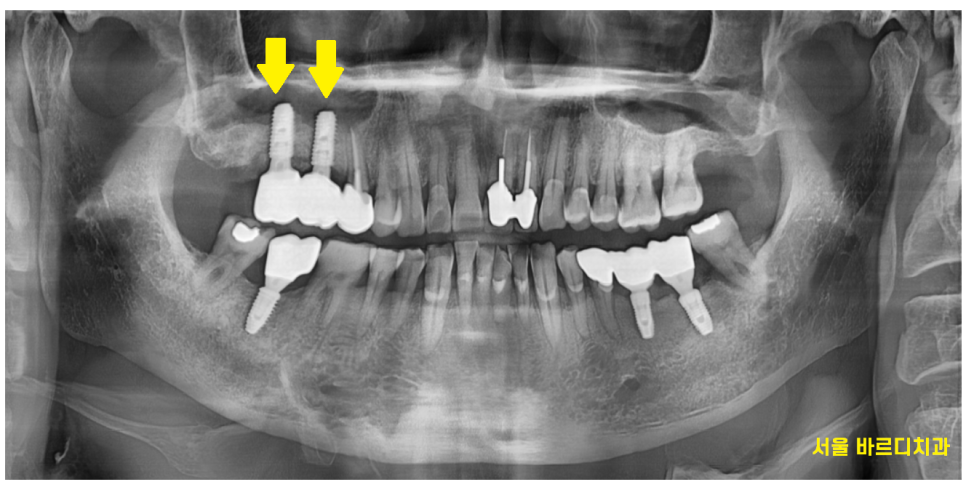

그래서 보철을 만들 때

신경써서 만들어드렸습니다.

24.01.23

볼이 밀고 들어오다보면

음식을 씹으면서

볼까지 씹을 수 있기에

보철 각도도 제작해주시는 소장님과

여러번 회의끝에

만들어드리며 치료는 끝이 났습니다.